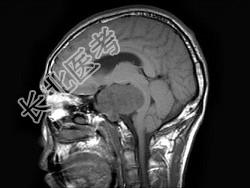

- 单项选择题男,38岁, 左侧面部麻木半年,头颅MRI见颅内占位性病变, 最可能的诊断为 ( )

B、三叉神经瘤